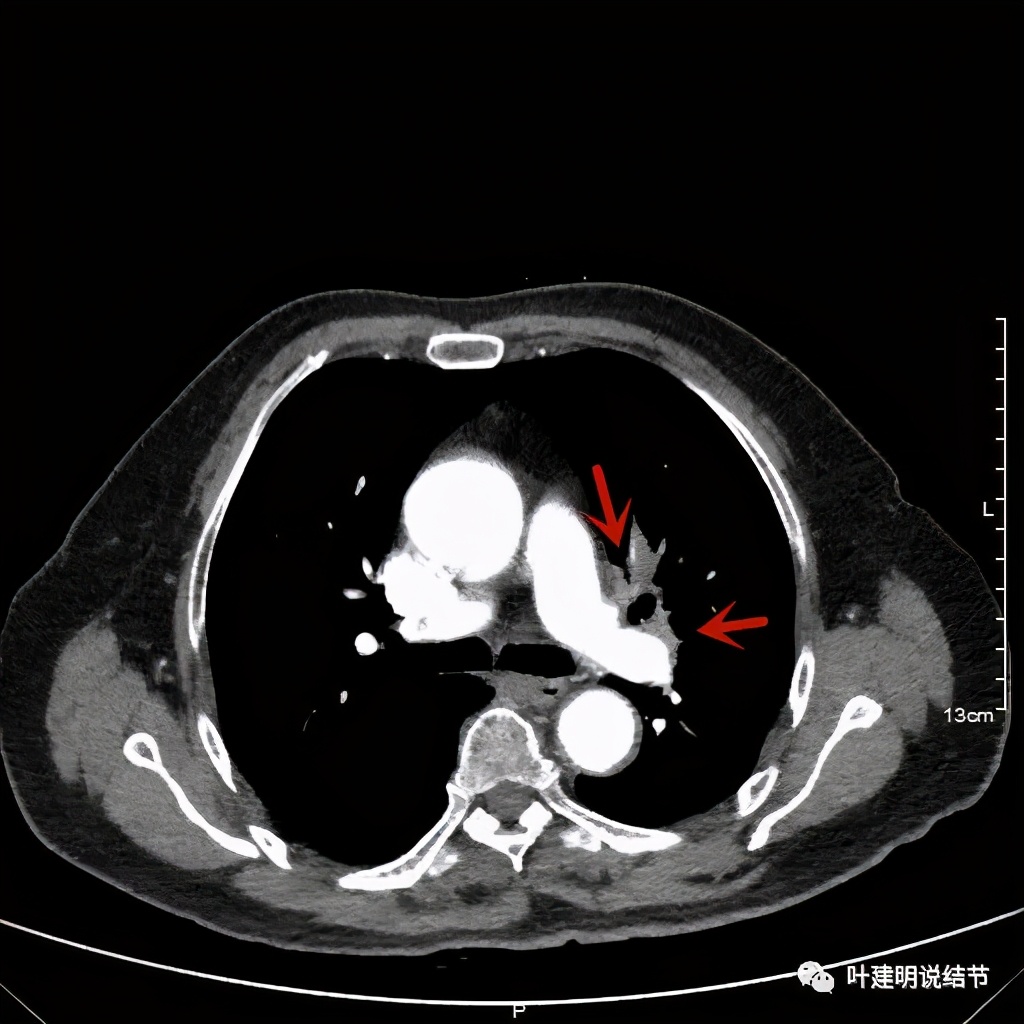

左上肺基本已经不见肿瘤,只在主动脉旁少许软组织影

上图示主动脉弓水平仍见软组织影

上图示肿瘤部位仍与肺动脉关系密切,似乎未能脱开,红色示肿瘤处